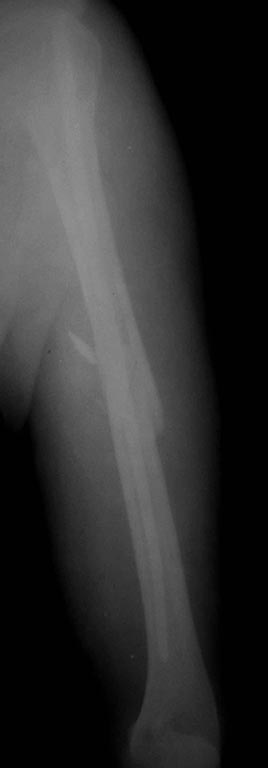

ближайший результат, все сделали закрыто, постараюсь сделать полноценные снммки - это палатником.

Сначала стабилизировали правую половину (крестец), вторым этапом сначала плечо, потом задние отделы слева, дальше аппарат спереди. Репозиция в положении на животе, свесил таз со стола, согнул ногу и тракция в этом положении.

аппарат недель на 6, но без нормального стола и ЭОПа делать проблематично, особенно крыло, толком проекции вывести не мог, прошел выше чем хотелось. Илиосакральные выинты тоже идут как-то подозрительно, хотя под ЭОПом выглядело все ОК, да и по ощущениям тоже (никаких провалов), надеюсь, что проекционно - неврологии не появилось.